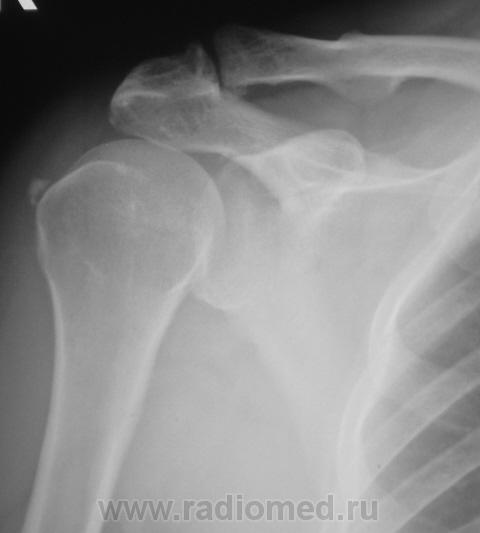

Пациентка направлена на рентгенографию плечевого сустава. Беспокоят боли в области плечевого сустава.

остеохондрома?

Плече-лопаточный периартроз(каменный бурсит)

поддерживаю оссифицирующий бурсит.

А руку вверх поднять невозможно.По снимкам оссифицирующий бурсит.

известковый тендинит сухожилия надостной мышцы, акромиально-ключичный артроз, внещний импинджмент с-м -извините, пишу как МРТ -шница.

+1 за артроз в ключично-акромиальном суставе(кроме известкового тендинита, естественно).

это экзостоз?, видно , что разрастание по нижнему краю ключицы  компримирует надостную мышцу и сдавливает ее в костном ложе, боль, наверное, усиливается при поднятии руки?

Да, пациентка отмечает появление боли при поднятии руки.

это может быть проявлением внешнего импинджмент с-ма. Импинджмент – можно истолковать разными способами: или как "сильное столкновение произошедшее вследствие удара или трения о какую-либо поверхность", "сильное влияние" или просто "вторжение".  Многообразие терминов соответствует многообразию симптомов проявляющихся в мышечно-скелетных расстройствах.Этот синдром возникает вследствие трения сухожилий вращательной манжеты об отросток лопатки – акромион, образующий верхнюю часть плечевого сустава. Имеется достаточный промежуток между акромионом и вращательной манжетой, так что сухожилия при движениях в плечевом суставе свободно скользят под акромионом. Однако всякий раз, когда вы поднимаете руку, происходит небольшое сдавление сухожилий и суставной сумки между головкой плечевой кости и акромионом.Первичный наружный импинджмент одно из наиболее часто встречающихся заболеваний плеча, обуславливающее 44-65% плечевых болей и рассматривается как результат субакромиального или субкоракоидального импинджмента, ассоциированного с патологией коракоакромиальной дуги, которая сформирована клювовидным отростком, корако-акромиальной связкой, акромионом, верхушкой лопатки и акромиально-ключичным суставом . Механизмы импинджмент не вполне ясны и мнения специалистов разделены на те, которые придерживаются наружной компрессионной теории и на те, которые придерживаются внутренней дегенеративной теорииНа ранних стадиях развития импинджмент-синдрома основной жалобой пациентов является разлитая тупая боль в плече. Боль усиливается при подъёме руки вверх. Многие пациенты отмечают, что боль мешает им уснуть, особенно если лежать на стороне пораженного плечевого сустава. Патогномоничным симптомом импинджмент-синдрома является возникновение острой боли у пациента при попытке достать до заднего кармана брюк. В более поздних стадиях боль усиливается, возможно появление тугоподвижности сустава. Иногда в суставе отмечается пощелкивание в момент опускания руки. Слабость и затруднение при поднятии руки вверх может свидетельствовать о разрыве сухожилий вращательной манжеты. Диагностика бурсита или тендинита, обусловленного импинджмент-синдромом основывается на анализе симптомов заболевания и физикального исследования. Боль над дельтовидной мышцей, усиливающаяся при отведении плеча против сопротивления наиболее часто диагностируется как импинджмент. Выполняется рентгенография плечевого сустава для выявления аномального или гипертрофированного акромиона или костных шпор около акромиально-ключичного сочленения. Если при осмотре будет заподозрен разрыв вращательной манжеты, то показано выполнение магнитно-резонансной томографии.